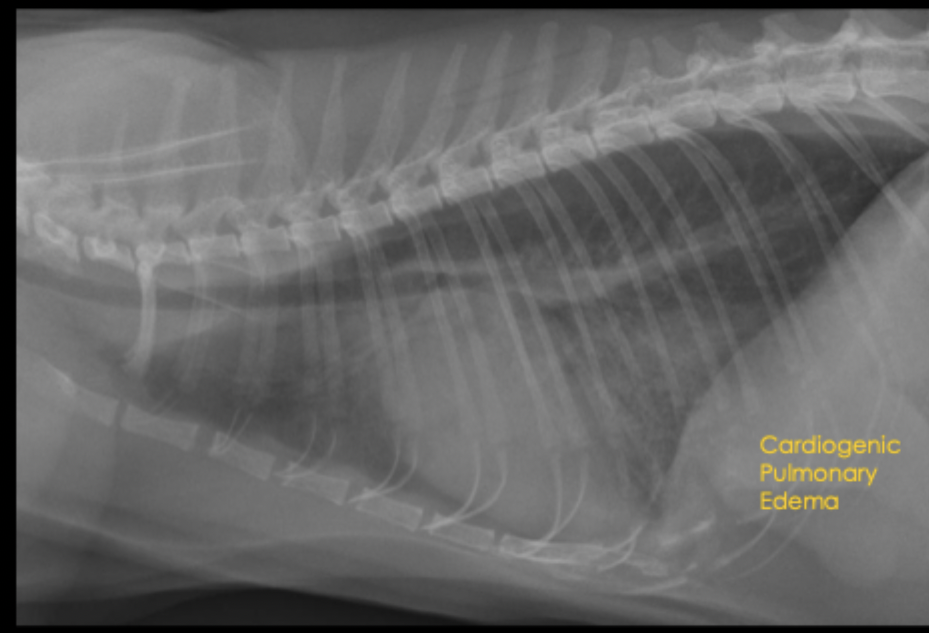

What is the radiographic appearance of cardiogenic pulmonary edema in dogs?

interstitial to alveolar pulmonary pattern in caudal lung lobes and perihilar region

pattern is patchy to diffuse

left atrial dilation, pulmonary vein dilation, cardiomegaly

A 9yo MC Cocker Spaniel mix presents for coughing and exercise intolerance. What is the primary pulmonary pattern?

primarily unstructured interstitial pattern

predominantly in the caudodorsal lungs and perihilar region

left worse than right

A 9yo MC Cocker Spaniel mix presents for coughing and exercise intolerance. Your primary pulmonary pattern is unstructured interstital but what other pattern is present?

focally more severe alveolar pattern

A 9yo MC Cocker Spaniel mix presents for coughing and exercise intolerance. What can be seen in this radiograph as far as heart features?

left sided cardiomegaly and left atrial enlargement

A 9yo MC Cocker Spaniel mix presents for coughing and exercise intolerance. What is your primary differential?

cardiogenic edema secondary to left sided congestive heart failure